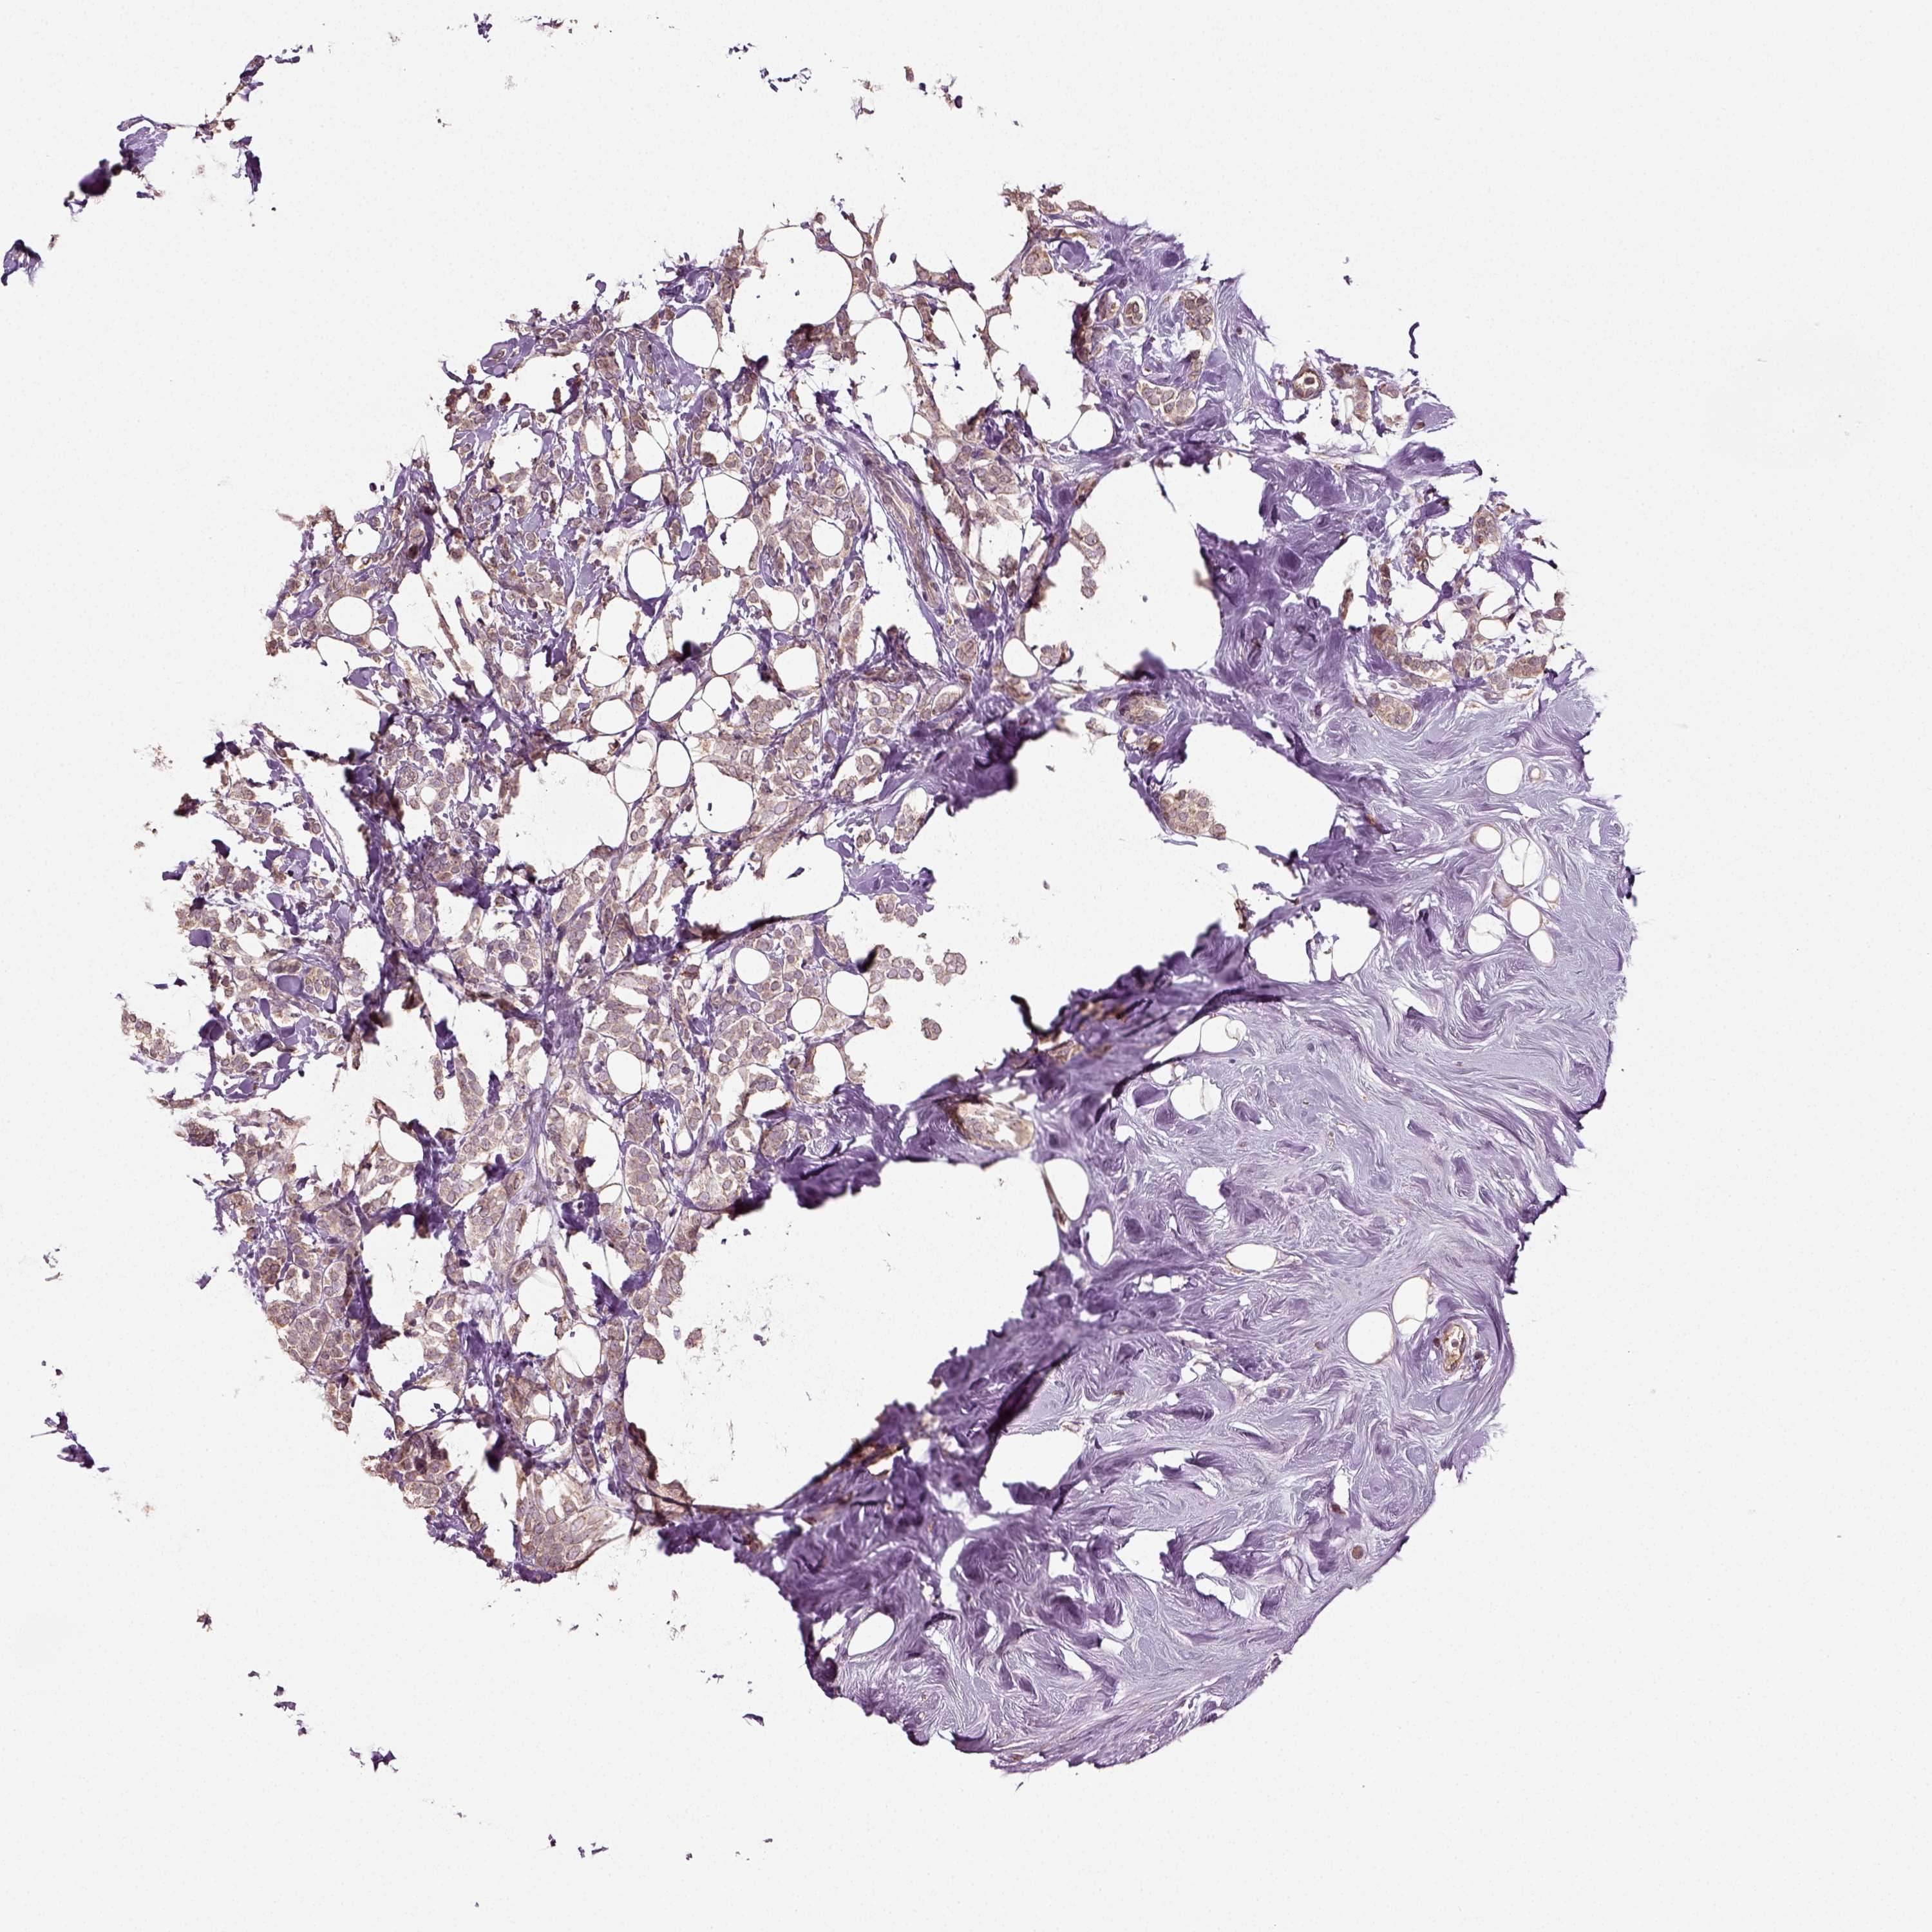

CANCER BREAST CANCER Show tissue menu

BRCA TCGA BRCA VALIDATION PROTEIN EXPRESSION